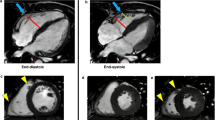

A graphical abstract (Fig. 4) summarizes the major findings in this manuscript.

Graphical abstract summarizing the major findings of the current study. Both apical and basal RV strain were measured in two study groups (DCM patients and NL subjects). The upper panel (A) is a diagram demonstrating 2 sites at the RV free wall for strain measurement. The red arrow & rectangle point to the RV apical segment; the green arrow & rectangle point to the RV basal segment. The lower two panels are 2 graphs illustrating RV-St apex mean value in DCM patients (B) and in normal subjects (C). A cut-off value ≤ 29.5% of the RV-St apex distinguished NL from DCM (sensitivity 91.2%, specificity 100%). [DCM: dilated cardiomyopathy, LA: left atrium, LV: left ventricle, NL: normal subject, RA: right atrium, RV: right ventricle/ventricular, RV-St apex: apical RV strain, RV-St base: basal RV strain]